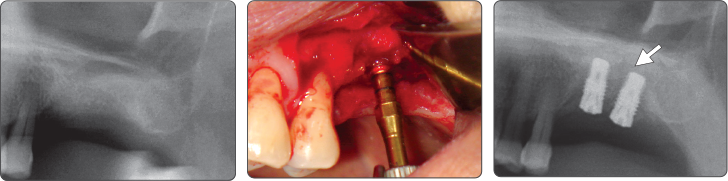

Sequence -Sinus Lift

Only use of Sinus Lift Drill

1. Sinus Lift (Ø4.0 Fixture)

▶ Immediate Implantation and Sinus Lift Technique with Tap Drill (Ø4.0 Fixture)

2. Sinus Lift (Ø5.0 Fixture)

▶ Immediate Implantation and Sinus Lift Technique with Tap Drill (Ø5.0 Fixture)

Recommend to use Sinus Lift Drill and Spreader Drill together